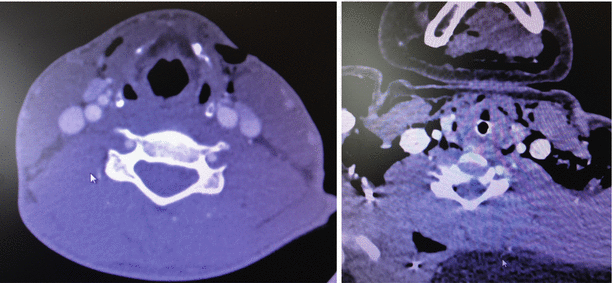

Fig. 32.2

Nondiagnostic CTA images for exclusion of pharyngoesophageal injury. Air near the pharynx and esophagus will require further evaluation if there are no other indications for surgical exploration

Computed tomography angiography (CTA) has emerged as the single imaging modality with the greatest potential to rule out esophageal as well as tracheal and vascular injuries. A missile trajectory away from the esophagus (or other vital structures) obviates the need for exploration or additional invasive studies. Beyond this, CTA has not yet proven itself as a stand-alone study for diagnosing or excluding pharyngoesophageal injury. In 2003, Gonzales evaluated 42 patients with CTA followed by mandatory esophagogram and operative exploration. Two very small stab wound injuries (<5 mm) were missed both by CTA and swallow study, suggesting that CTA was no better than esophagogram. Inaba subsequently found that CTA “overdiagnosed” aerodigestive injury in four patients with subcutaneous air as the common, nonspecific sign. Two patients had the injuries ruled out by negative contrast swallows and endoscopy. The other two patients underwent negative exploration. Most centers are using physical examination along with CTA to evaluate for a possible aerodigestive injury. Finding air near the pharyngoesophagus prompts the need for further study, surgical exploration, or both (Fig. 32.2).